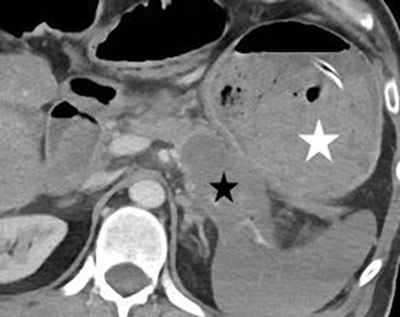

Figure 3

Axial contrast-enhanced CT image: the pancreatic neoplasm (black star) and the almost entirely clotted gastric lumen (white star).